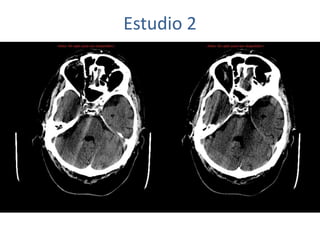

Estudio 2

• Estudio sin y con contraste, con reconstrucciones sagitales y coronales

del estudio con contraste.

Se observa una lesión ocupante de espacio en lóbulo frontal derecho que

presenta un tamaño de 18 x 32 x 22 mm (cc x ap x tr), bilobulada, no del

todo bien delimitada, con realce en anillo irregular, con hipocaptación

central, probablemente por necrosis, y asociada a un extenso edema

vasogénico con efecto masa tanto sobre los surcos de la convexidad

como sobre la cisterna insular, el sistema ventricular y la línea media,

esta última con un desplazamiento de 5 mm a la altura del septo

interventricular.

No se aprecian otras lesiones focales intra o extraaxiales de significación

patológica.

Habría que considerar como primera posibilidad que se tratase de una

lesión metastásica, por bien un tumor primario, aunque no se puede

descartar otras opciones, sin imprescindible correlación con la clínica y

con sus antecedentes.